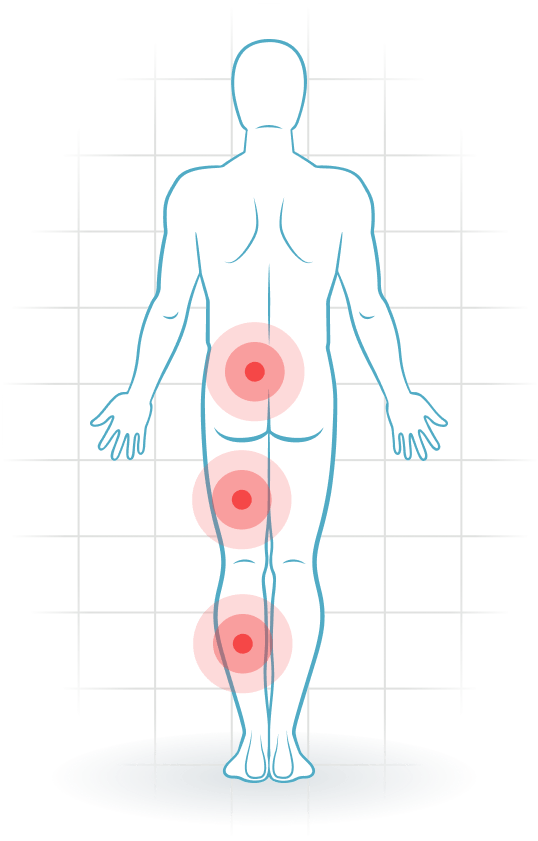

Nevrogen claudicatio

- Du har smerte og en annerledes følelse i beina etter å ha gått eller stått en stund.

- Plagene forverres ved å strekke ryggen (lage svai).

- Plagene lindres ved å bøye ryggen (lage krum).

Dette er typiske symptomer på Lumbal spinal stenose. Fremskynd bedringsprosessen med riktige fysioterapiøvelser.